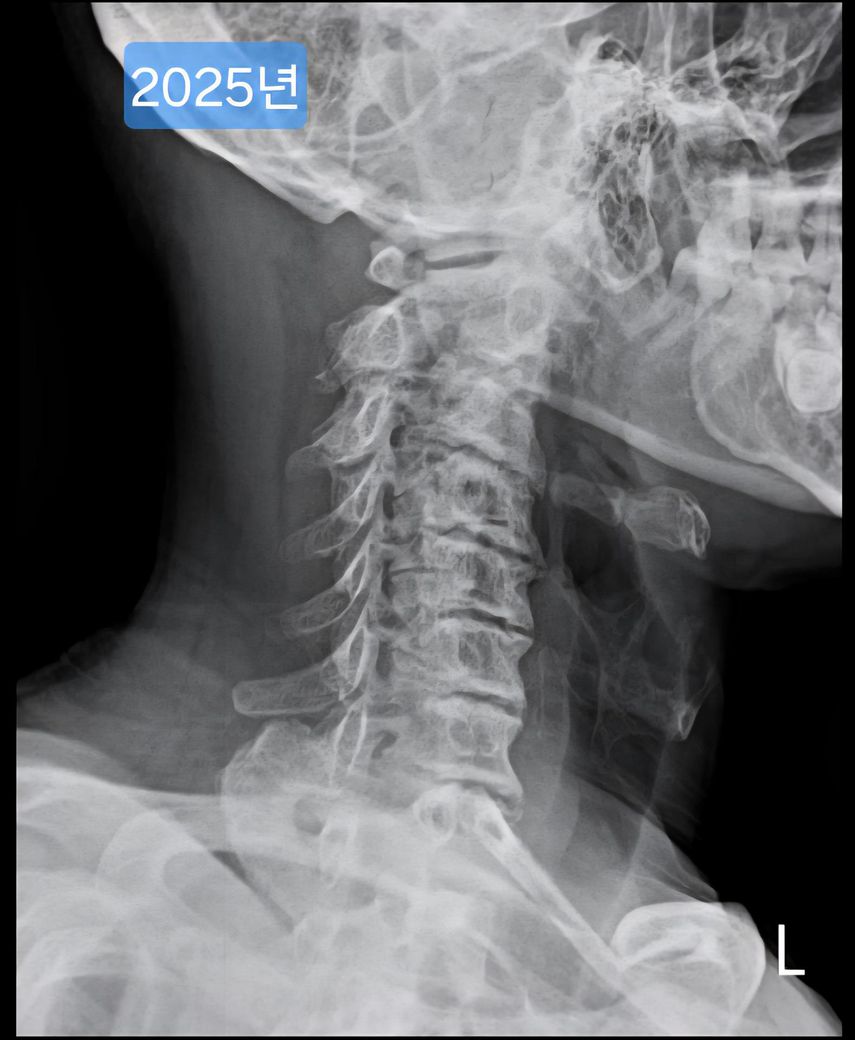

일자목, 경추사이 공간이 좁은 안좋은 형태의 목상태 입니다